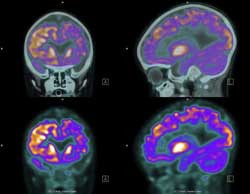

L’epilessia, che affligge milioni di persone in tutto il mondo, è una condizione per cui nel cervello si verificano crisi spontanee imprevedibili. Questa condizione, potenzialmente pericolosa, avviene a causa di una comunicazione anomala tra le reti neuronali nel cervello.

La nostra conoscenza del ruolo dei microcircuiti neurali (o neuroni hub) nell’attività epilettica è molto limitata. Per identificare quali cambiamenti causano l’epilessia, il progetto HUBS IN EPILEPSY (“Functional connectivity and the role of hub neurons in epilepsy”), finanziato dall’UE, ha studiato la loro struttura funzionale e anatomica nel cervello. I ricercatori miravano a identificare gli elementi chiave nei microcircuiti neurali che causano l’epilessia. A tal fine hanno utilizzato imaging del calcio in vitro e in vivo ed esami istologici del tessuto epilettico. Il modello di topi trattati con pilocarpina per l’epilessia lobo-temporale è stato scelto per la sua somiglianza alla patologia cerebrale umana. I risultati hanno collegato l’attività epilettiforme alla co-attivazione di assemblaggi neuronali localizzati nello spazio. Ma si è anche scoperto che l’attività epilettica ricorrente era dovuta alla co-attivazione di gruppi differenti di neuroni anziché degli stessi sottoinsiemi di neuroni. Contrariamente a una precedente ipotesi, gli interneuroni GABAergici (dell’acido gamma-amminobutirrico) nell’ippocampo svolgono un ruolo chiave nelle scariche interictali. Le scariche interictali sono i segnali che si vedono in un elettroencefalogramma nel periodo tra crisi o episodi epilettici. Per chiarire l’epilettogenesi (la transizione di un cervello normale nell’epilessia) i ricercatori hanno utilizzato immunoistochimica su campioni di tessuto di topi epilettici. Malgrado la diffusa morte cellulare durante l’epilettogenesi, i neuroni GABAergici o glutamatergici formatisi precocemente sopravvivevano. Le attività del progetto hanno fornito nuove conoscenze sui meccanismi alla base dell’epilessia su microscala. Ulteriori sforzi della ricerca in questo campo si possono ora concentrare sulla caratterizzazione del ruolo dei neuroni GABAergici o glutamatergici nell’attività epilettiforme. Queste scoperte potrebbero portare anche allo sviluppo di terapie più efficaci per questa condizione disabilitante.